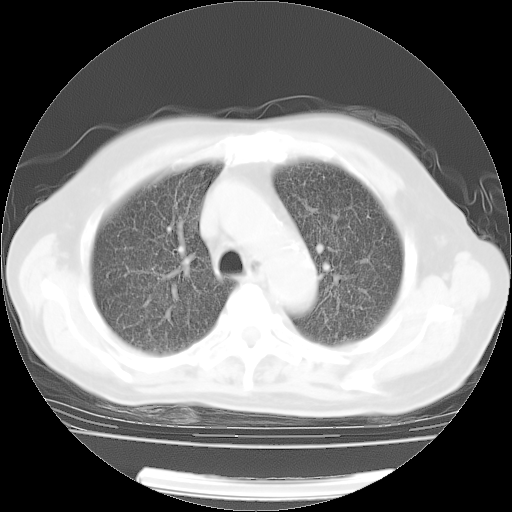

肺部CT平扫未见异常。